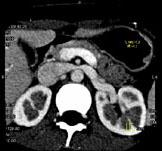

问题 女,24岁,发作性肉眼血尿1年,实验室检查:尿蛋白(-+)、红细胞(12/HP),尿蛋白直立试验(+),CT扫描如图,下列说法正确的是 ( )

选项 A.双肾大小形态正常 B.左肾静脉走行至肠系膜上动脉与腹主动脉间变细,近左肾处扩张 C.左侧肠系膜上动脉与腹主动脉夹角变小 D.左侧肠系膜上动脉与腹主动脉夹角增大 E.考虑为左肾静脉胡桃夹综合征

答案 ABCE